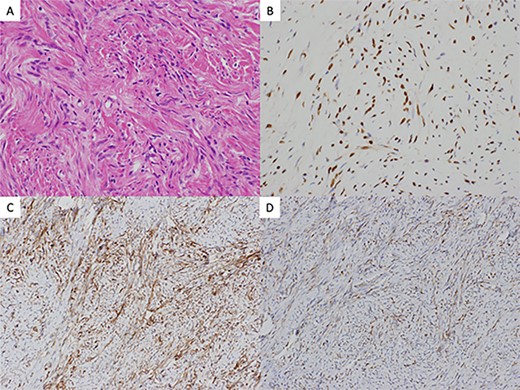

Postoperative histological findings showed 34-mm firm and round tumor, and well circumscribed without involving the visceral pleura. The pathologic examination revealed proliferating spindle-shaped cells with a random fascicular arrangement with continuity to the pulmonary interstitium (Fig. 2A). Not much cellular atypia was observed. Immunohistochemical staining indicated that the tumor was positive for STAT6 (Fig. 2B), CD34 (Fig. 2C), bcl-2 (Fig. 2D) but negative for cytokeratins, EMA, CD99, S-100. The WHO classification for SFT grade uses the presence of dense cellular regions and multiple fissions (>4 mitoses/2 mm2) as diagnostic criteria [2]. In this case, there was no visible necrosis and mitoses were infrequent. The final diagnosis was an intrapulmonary benign SFT. Three months after the surgery, the patient is under outpatient follow-up with no recurrence.

(A) histology hematoxylin and eosin staining of the resected tumor revealed proliferating spindle-shaped cells with a random fascicular arrangement with continuity to the pulmonary interstitium (×40). Immunohistochemical findings revealed the tumor cells to be positive for (B) STAT6 (×200), (C) CD34 (×200), and (D) bcl-2 (×200)